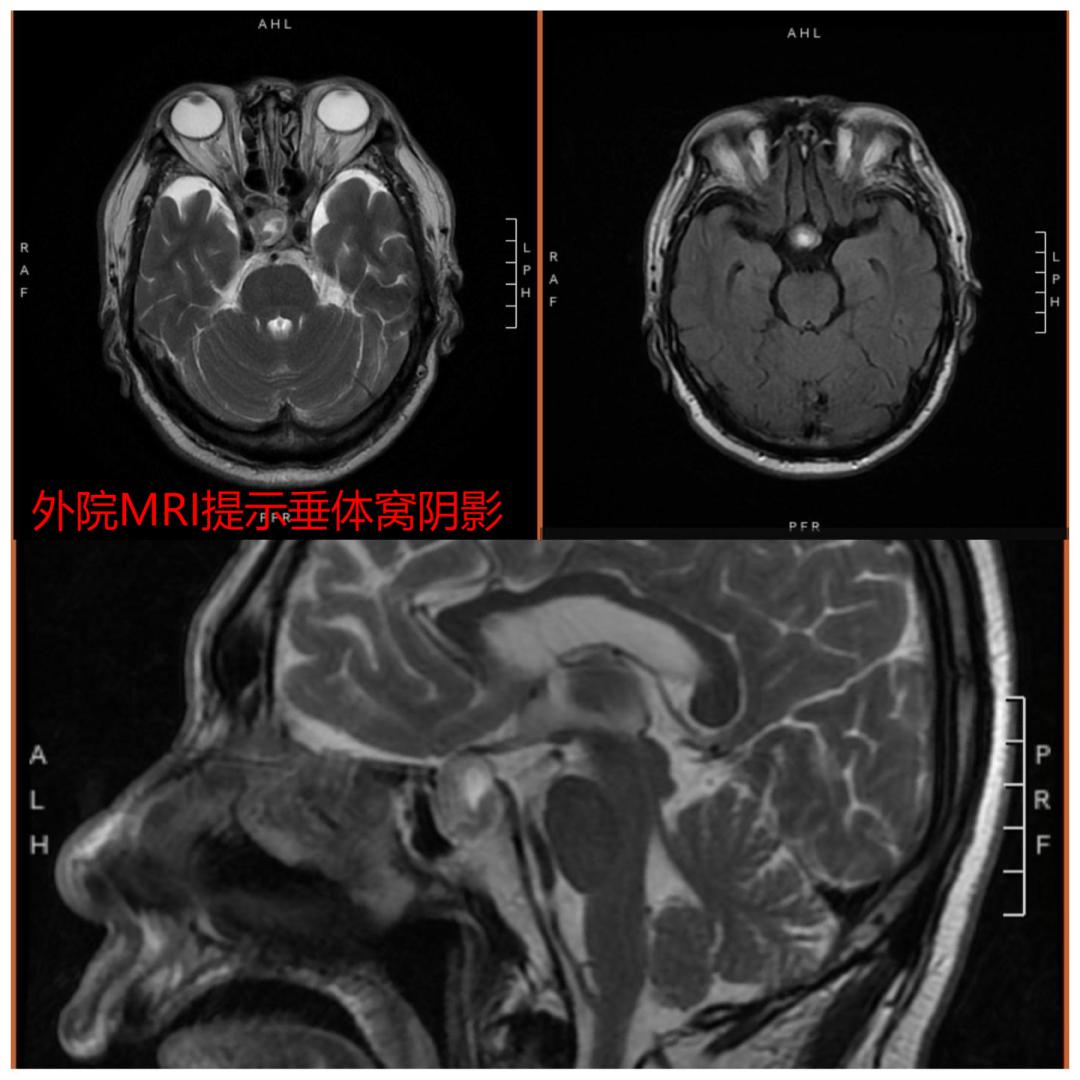

70岁的魏大爷是桓台县唐山镇的一名和善的老人,6月中下旬的一天,魏大爷突然出现右侧头顶的剧烈头痛,并且两只眼睛的视力迅速下降。家里的儿女们不敢怠慢,当天就把魏大爷送到了县里的医院住院治疗。眼科检查后并没有发现明显的问题,但是大爷的头痛和视力下降却明显加重,并且右眼已经逐渐失明!最后的颅脑核磁共振终于有了提示,垂体窝内有近2cm的混杂的信号影,怀疑肿瘤。县里的医院对这个疾病没有太多的认识,也不具备相应的设施进一步检查和治疗。家里人才把魏大爷送到了淄博市中心医院东院急诊科。

通过追问病史,原来大爷半年前查体时就发现了垂体窝内有约直径1cm的阴影,但是由于没有任何症状,就没再继续到上级医院进一步诊疗。“所以这个基本上就能判定,是约1cm的脑垂体瘤突然出血体积明显增大,直径增大了1倍导致了头痛,而且直接压迫视神经的视交叉部分导致右眼的失明。”